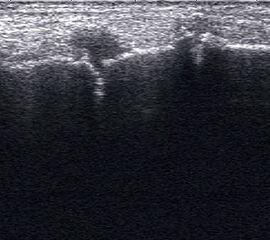

Dorsaler TS hinter dem Innenknöchel.

Abbildung 46

Lagerung: Rückenlage, Außendrehung des Beines.

Schnittführung: TS und LS hinter dem Innenknöchel beginnen und bis zum Os cuneiforme mediale fortführen.

Referenzstrukturen: Innenknöchel, Talus, Os naviculare, Os cuneiforme mediale, Sehnen der Mm tibialis posterior, flexor hallucis longus, flexor digitorum.

Befunde: Häufig betreffen die Pathologen die Tibialis-posterior-Sehne, die als erste Sehne hinter dem Innenknöchel zur Darstellung kommt. Halo-Phänomen und echoarme Verdickung bei akuter Tendinopathie, zunehmend inhomogen und echogen mit Kaliberschwankungen bis hin zu Teilrupturen bei Chronifizierung 5. Für die Erkennung von Teilrupturen sind TS in verschiedener Höhe besonders wichtig. Bei komplettem Riss mit Retraktion im LS Bild wie Spargelspitze mit umgebender Flüssigkeit oder Hämatom. Ein Os tibiale externum erscheint als echoreiche Struktur im Verlauf der Tibialis posterior Sehne mit dorsaler Schallauslöschung. Ein Os naviculare cornutum imponiert als starke Prominenz im Ansatzbereich der Tibialis posterior Sehne.